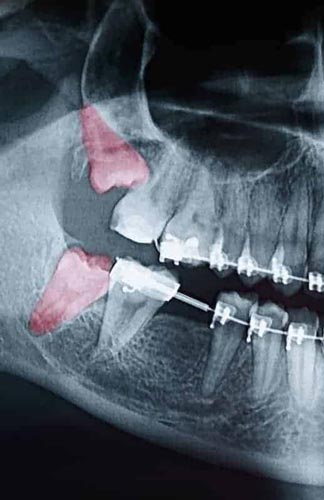

Most people have enough room in their mouths for 28 teeth. When four additional molars start to come in, usually in the late teens and early 20s, it can cause problems for some. This includes crowding, coming in sideways, soreness, risk of infection, and becoming stuck beneath the gum and bone. When wisdom teeth don’t erupt through the gumline properly, they can create severe problems, including:

- Risk of infection in tissues surrounding the tooth

- Disruption to the orthodontic or natural alignment of teeth

- Formation of tumors or cysts around impacted wisdom teeth, resulting in jawbone or tooth destruction.

We evaluate patients’ wisdom teeth before they start to come in, using X-rays to monitor their formation and progress. If the teeth show signs of causing complications, we suggest having them removed. Since early treatment is beneficial to patients, we recommend children be evaluated when they are in their mid-teens.